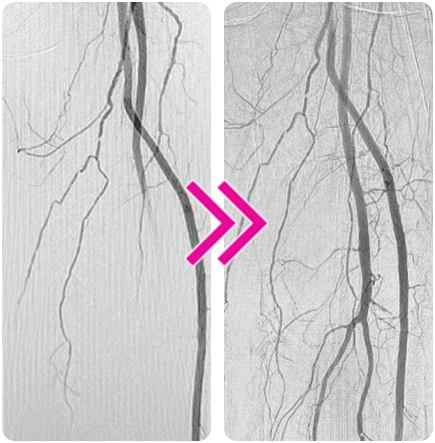

Successful Removal of Bilateral Embolization Using the Pounce™ Thrombectomy System

Bruce H. Gray, DO, MSVM

A 44-year-old woman who worked as a mail carrier presented with a 4-week history of claudication. She had no risk factors for atherosclerosis, was in normal sinus rhythm, and had no history of medical illness.